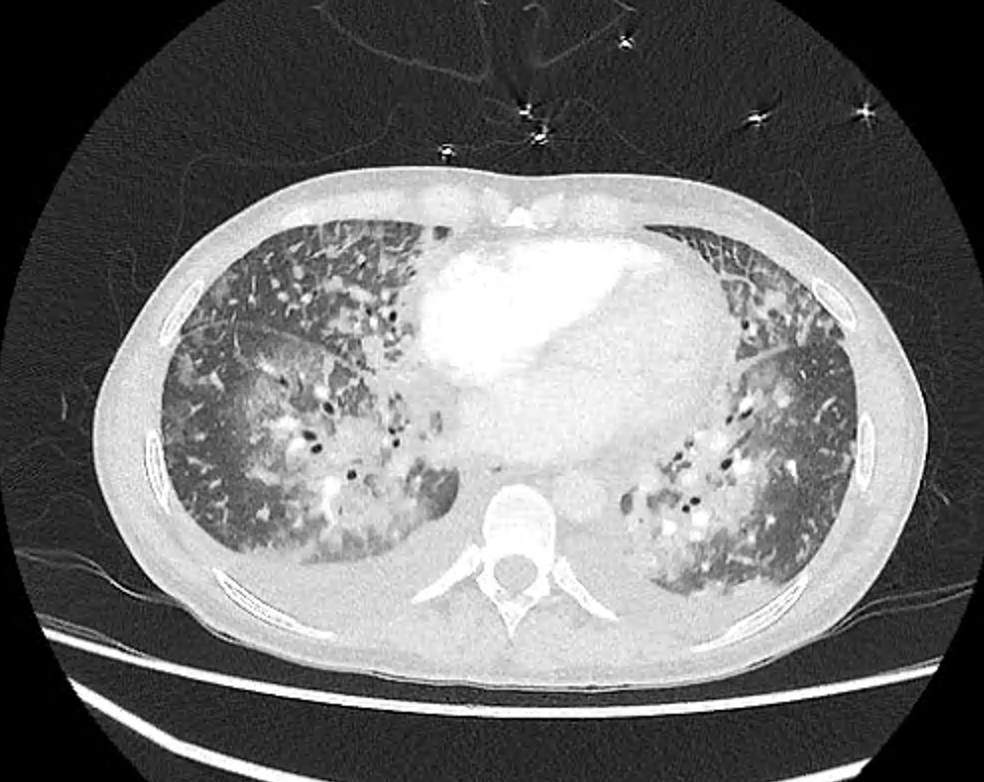

Here’s another case.

A lady in her 30s is intubated in the ED with progressive respiratory distress, initially thought to be severe bilateral pneumonia with markedly raised inflammatory markers.

A bedside echo tells a different story 👀

• Anterior mitral valve vegetation

• Mitral valve perforation

• Resulting in severe acute MR

She was transferred to a tertiary centre where she underwent urgent mitral valve replacement.Image